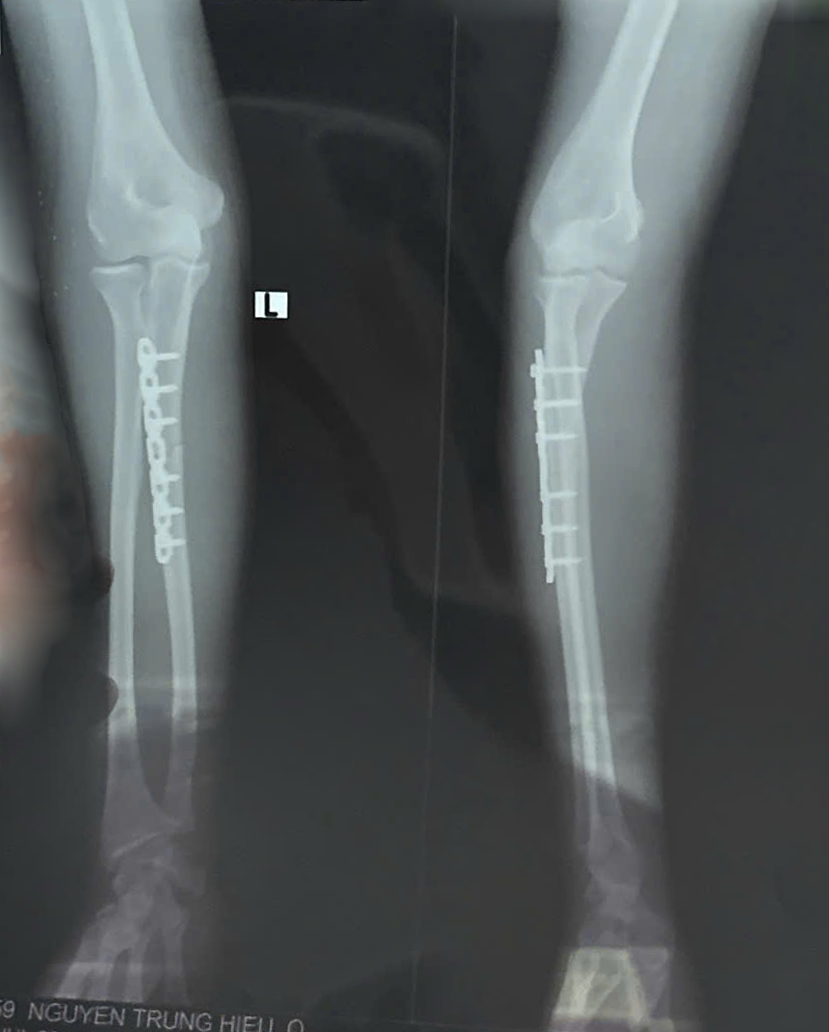

( Hình ảnh phim Xquang của Bệnh nhân)

- được phẫu thuật kết hợp xương nẹp vít cố định xương trụ và chuyển sang Phòng Hoạt động trị liệu – Khoa PHCN-YHCT thuộc Bệnh viện Chỉnh hình và Phục hồi chức năng Cần Thơ.